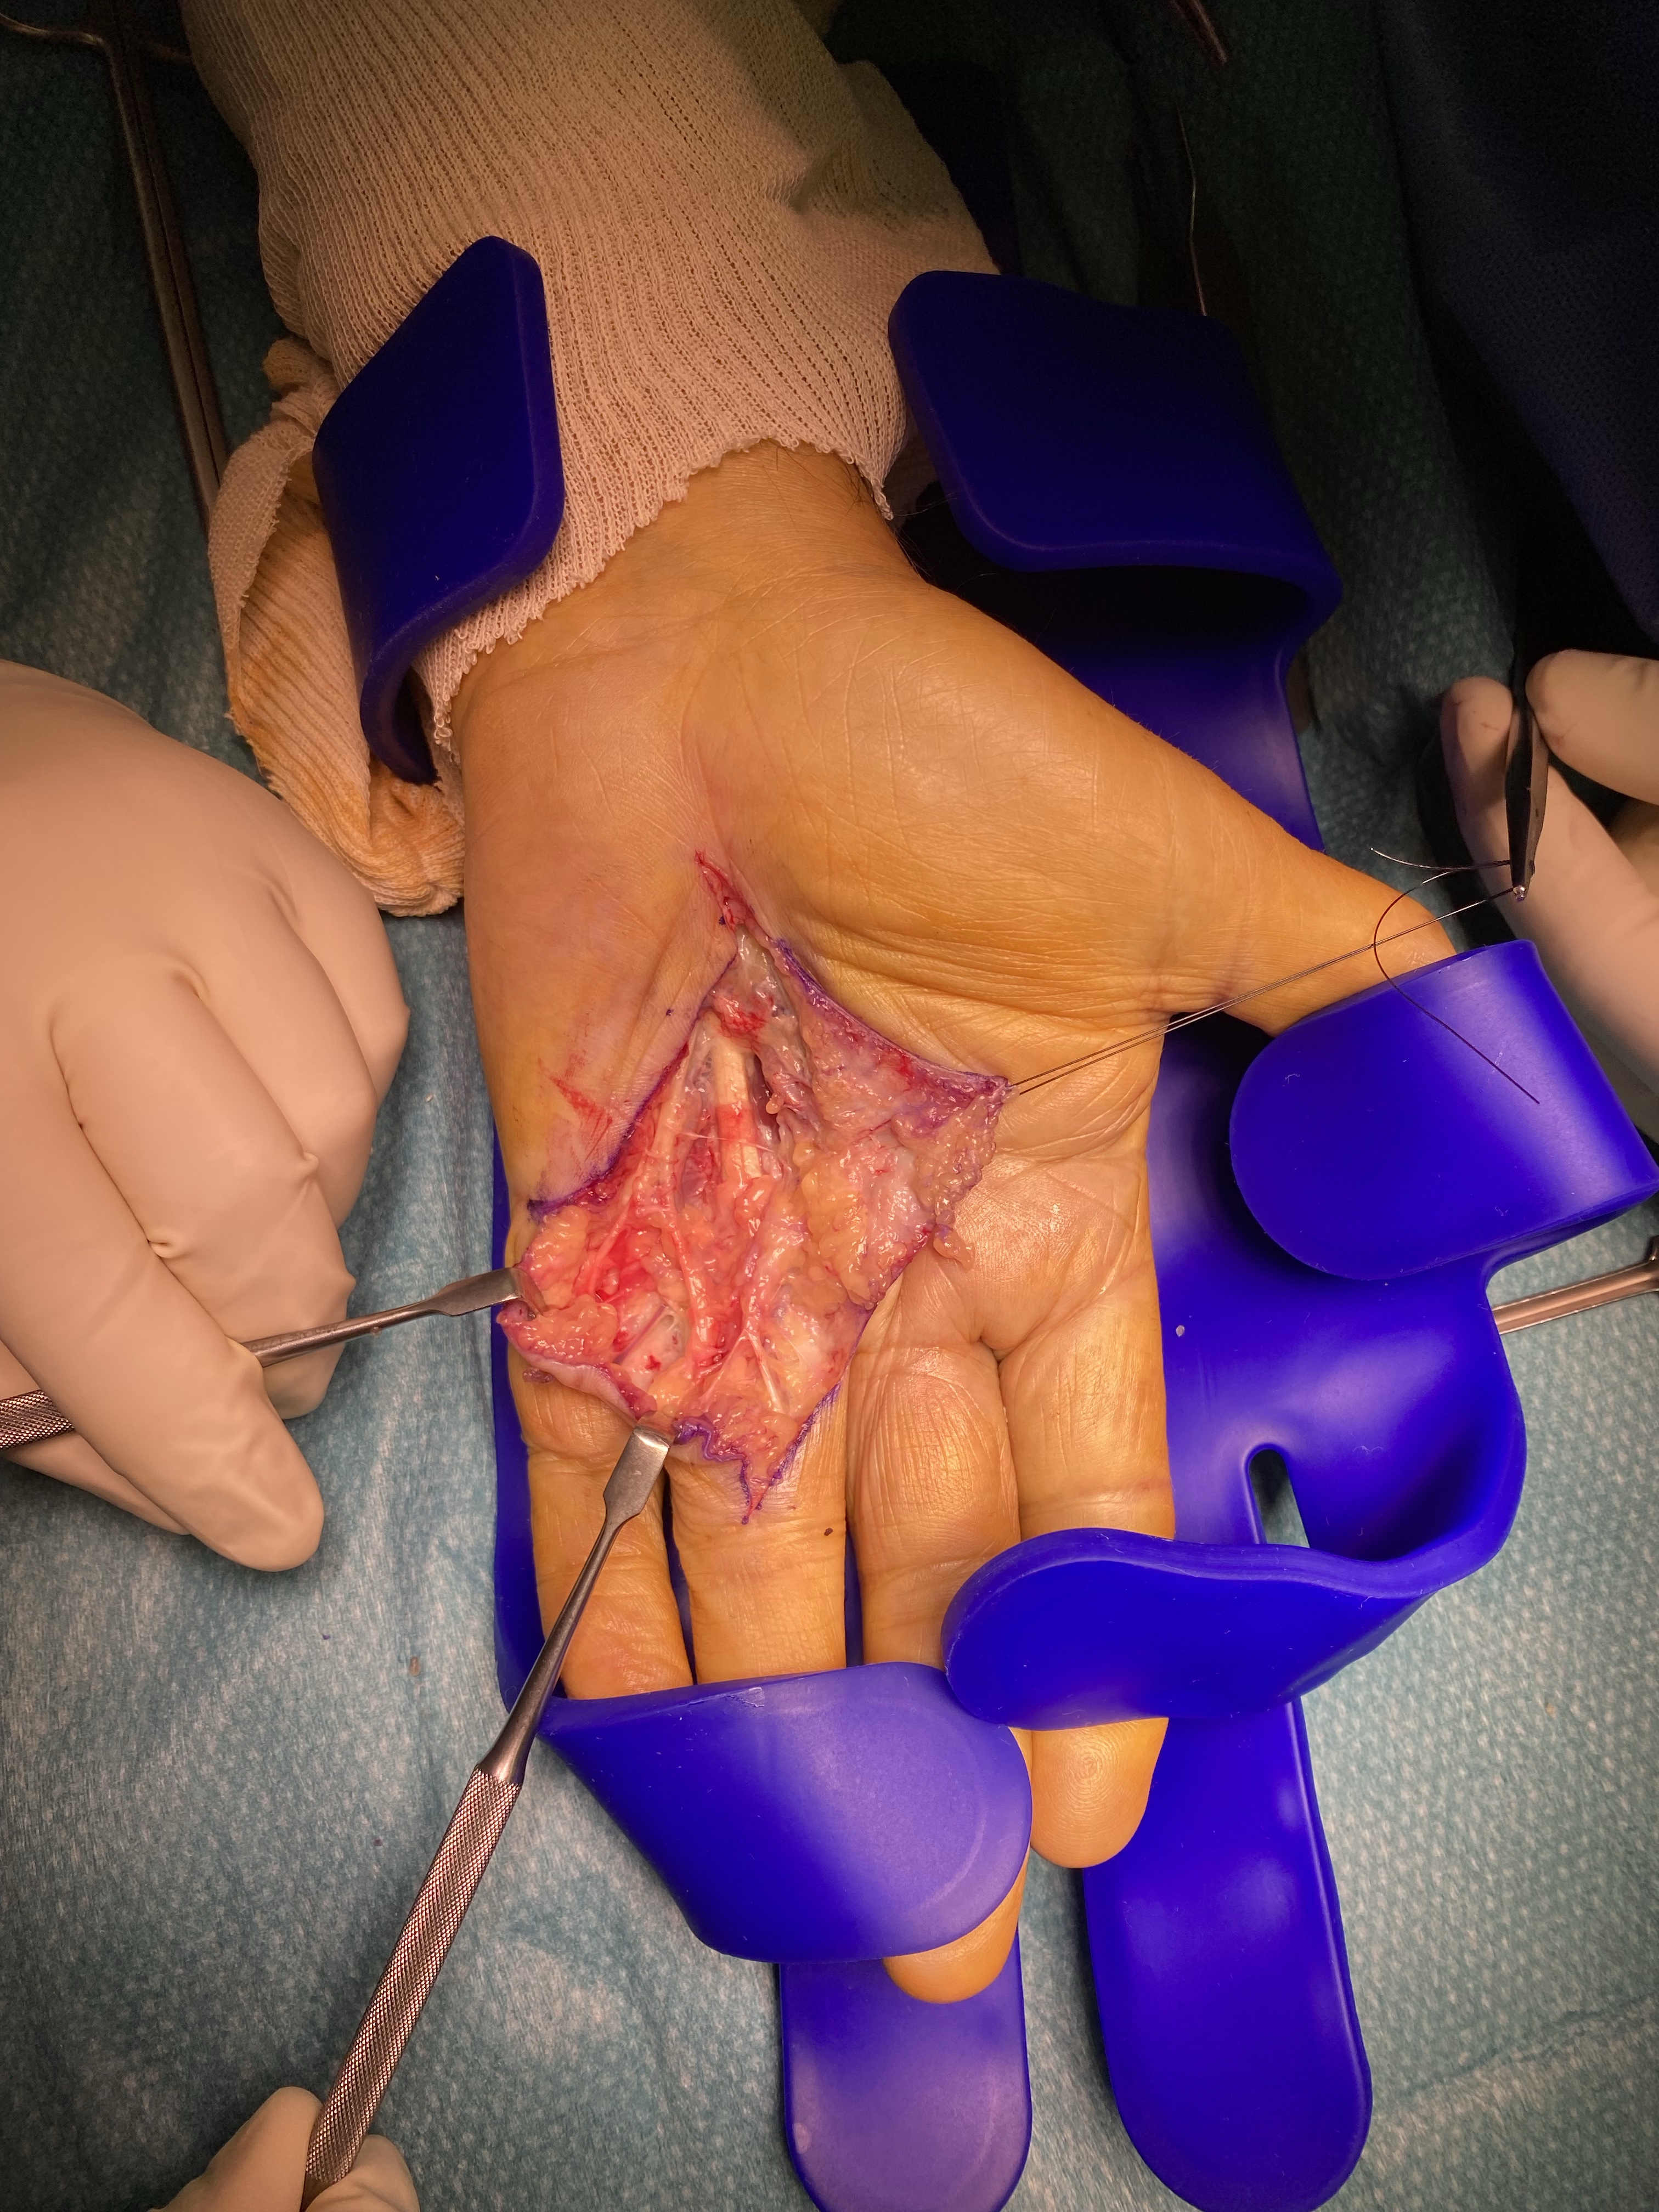

Après vous avoir installé, et mis en place des champs stériles, le chirurgien réalisera le geste prévu.